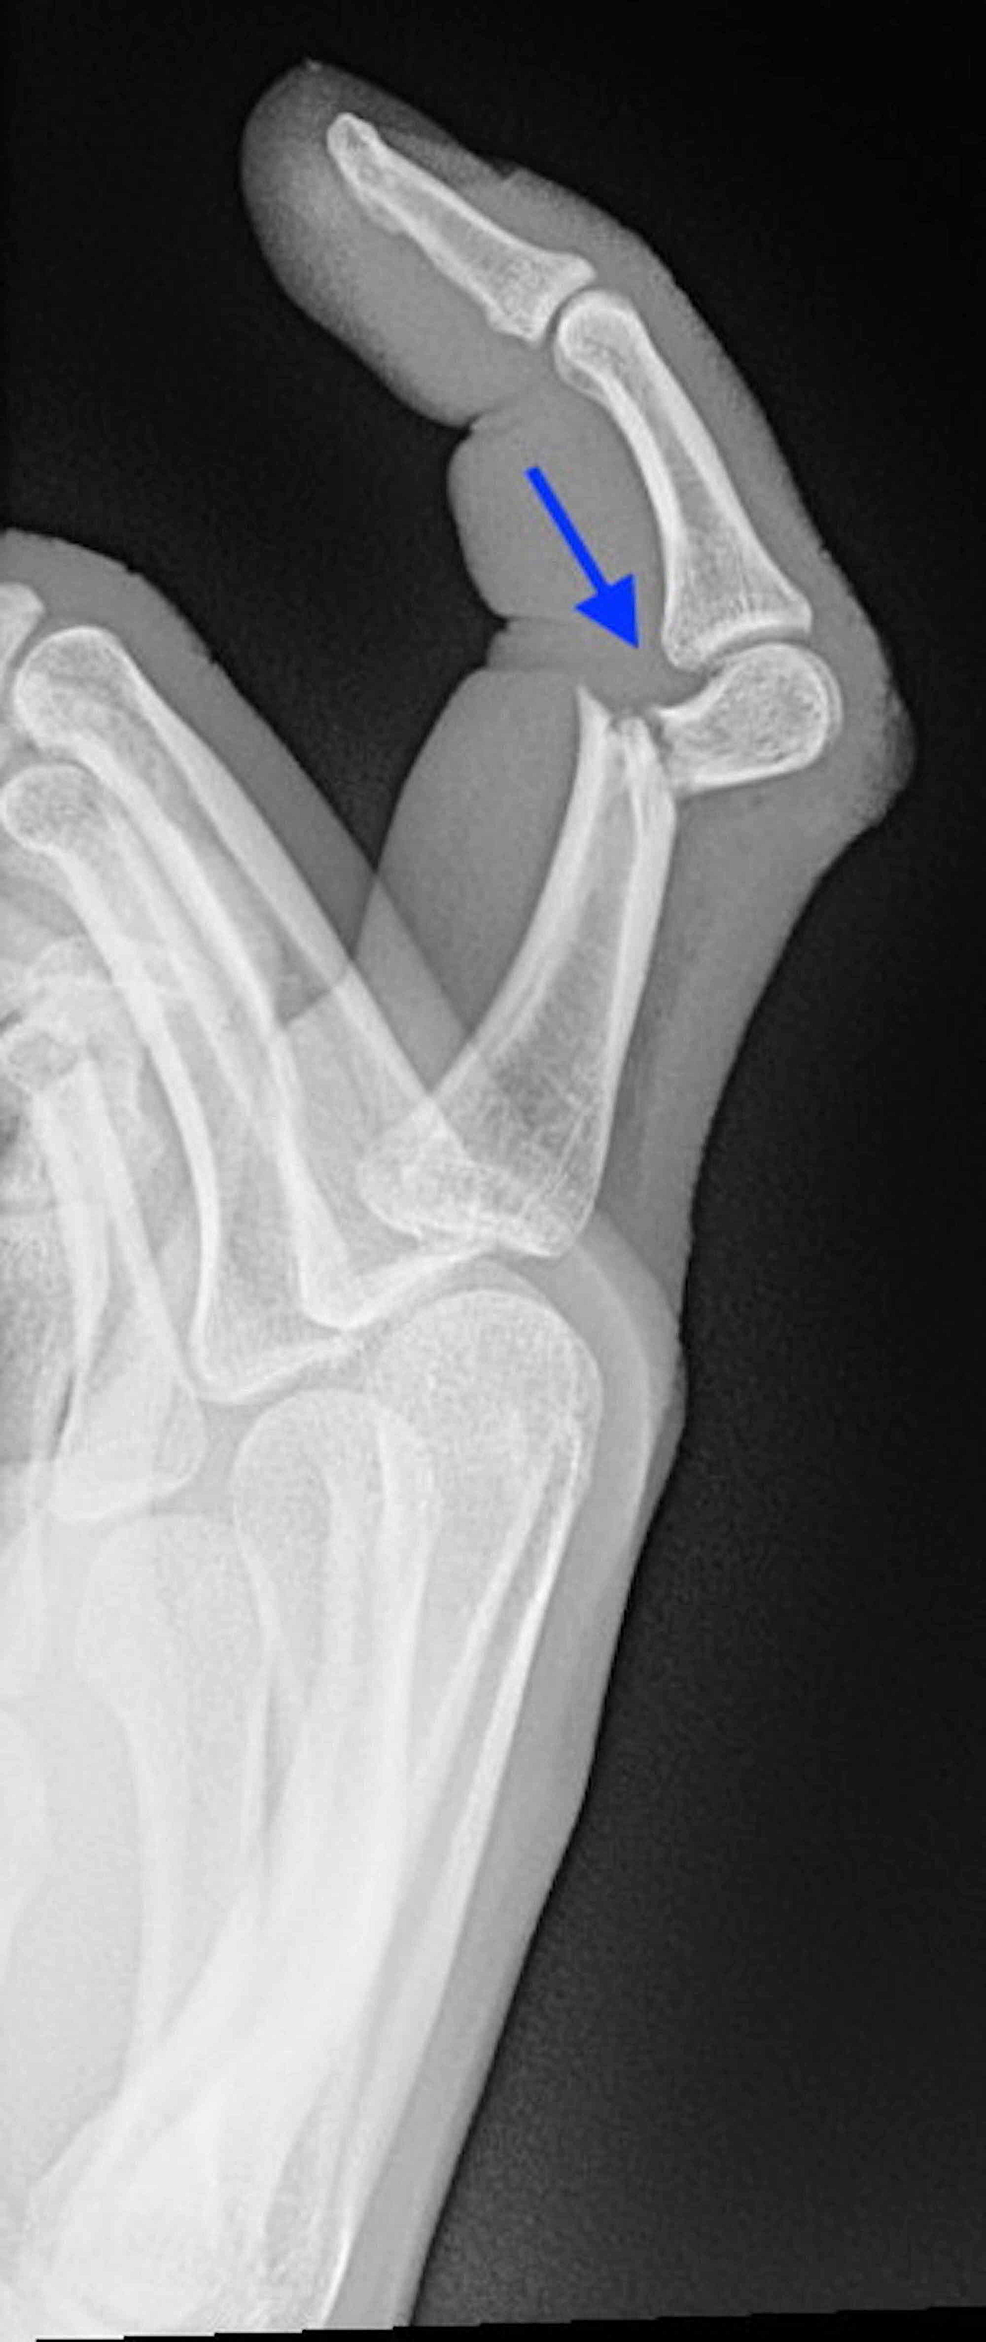

발가락만큼이나 손가락 역시 일상에서 쉽게 골절이 발생하는 부위입니다. 손가락 골절은 대개 손을 이용해 무거운 물건을 받치거나, 야구‧배구 같은 스포츠 활동 중 충격을 받았을 때 생깁니다. 손가락은 정교한 동작을 수행해야 하므로, 치료와 재활 과정이 특히 중요합니다.

깁스 vs 스플린트 vs 핀 고정 수술

- 핀 고정 수술

- 뼈가 복합적으로 부러지거나, 어긋나서 그대로 붙으면 기능에 치명적 문제가 예상되는 경우에는 핀이나 금속판을 삽입하는 수술을 진행합니다.

- 수술 후에는 손가락 움직임을 최소화하고, 적절한 시점에 재활 운동을 시작해야 합니다.